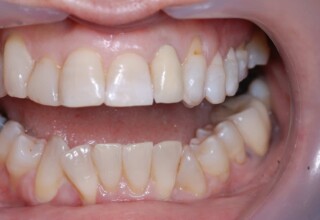

Οι όψεις πορσελάνης είναι ο καλύτερος τρόπος αντιμετώπισης αισθητικών προβλημάτων στην πρόσθια περιοχή του στόματος. Συνδυάζουν συντηρητική αφαίρεση οδοντικής ουσίας και πολύ υψηλή αισθητική απόδοση. Στο παρακάτω εκτεταμένο περιστατικό υπήρχαν: παλαιά σφραγίσματα, δυσχρωμίες, κακό σχήμα και μήκος δοντιών, κακή αναλογία δοντιών-ούλων. Έγινε προσεκτικός εργαστηριακός σχεδιασμός σε εκμαγεία απ’όπου προέκυψαν προσωρινές όψεις που τοποθετήθηκαν στο στόμα για δοκιμή και διορθώσεις. Όταν οριστικοποιήθηκαν οι μετατροπές, οι προσωρινές χρησιμοποιήθηκαν σαν οδηγός για τις μόνιμες. Οι πέντε μόνιμες όψεις πορσελάνης που κατασκευάστηκαν για τα πέντε πρόσθια δόντια της άνω απεκατέστησαν σχεδόν άψογα την αισθητική εμφάνιση της ασθενούς.

Αρχική εμφάνιση

Τελική εμφάνιση